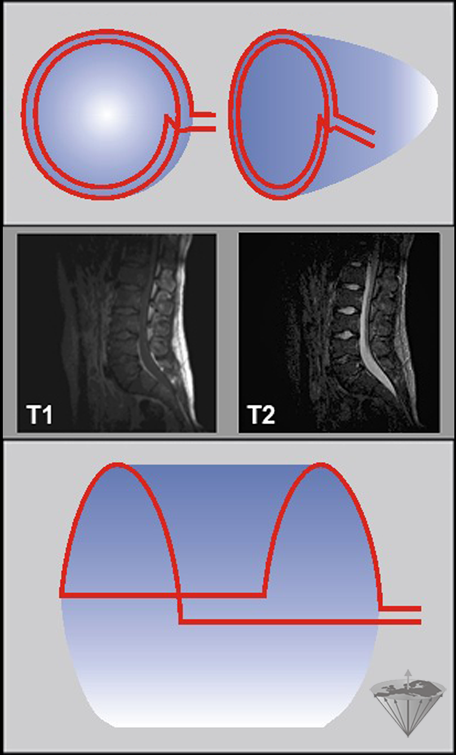

Figura 03-13:

Bobinas de superficie

Arriba: Diagrama de una bobina de superficie simple. Dado que la intensidad del campo de RF varía en relación con la profundidad, el ángulo de pulso también variará en relación con la profundidad a menos que se utilicen pulsos especiales (adiabáticos). Igualmente, la sensibilidad de detección también será menor a mayor profundidad.

Centro: Imágenes potenciadas en T1 y T2 de la columna lumbar adquiridas con bobinas de superficie. La médula y la columna vertebral se aprecian bien pero casi no hay señal proveniente de las partes anteriores de la pelvis.

Abajo: Bobina de superficie envolvente (en inglés wrap-around) o de media silla de montar.